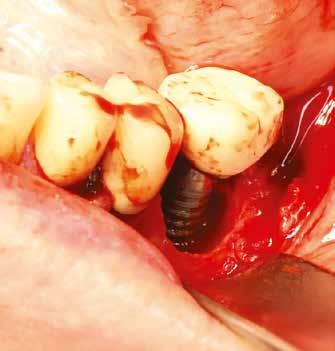

1. ábra: A műtét előtti szituáció, megfigyelhető az implantátumok közötti konkáv terület, ahova könnyen beragad az ételmaradék, és könnyen kialakul a periimplantitis.

Egy 47 éves páciens jelentkezett nálunk egy alsó, hátsó foghiánnyal, ahol jelentős csontfelszívódást tapasztaltunk a moláris fogak korábbi eltávolítása miatt (1. ábra). Két implantátum körül is volt ínyrecesszió, illetve a keratinizált íny mennyisége minimális volt (kevesebb, mint 1 mm). 4 hónappal az implantációt követően ínykorrekciót végeztünk.